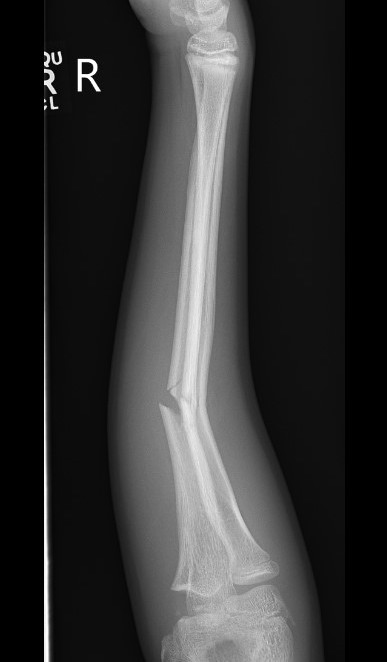

Types

Complete

Greenstick

Buckle / torus

Single or both bone

Galeazzi / Monteggia

Non Operative Management

Acceptable Position

< 10 years old: < 15 degrees malalignment

> 10 years old: < 10 degrees malalignment

< 1 - 2 years of growth remaining: Anatomic alignment required

Operative Management

Indications

Outside parameters for non-operative treatment (see above)

Loss of reduction

Options for displaced fractures

1. MUA

- young patients < 10

- greenstick fractures